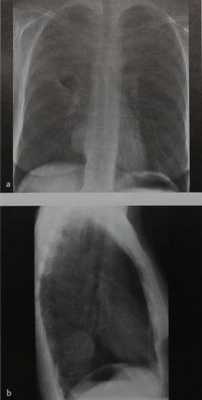

Неврилеммома у мужчины 48 лет. На обзорной рентгенограмме грудной клетки видно округлое образование с гладкими контурами, расположенное паравертебрально в нижнем отделе заднего средостения. Даже в отсутствие расширения межпозвонкового отверстия локализация объемного образования дает основание думать, что оно, скорее всего, имеет нейрогенное происхождение. Диагноз неврилеммомы подтвердился на операции.

Нейрофиброма у женщины 38 лет.

На обзорной рентгенограмме грудной клетки верхний отдел средостения расширен в обе стороны, но больше слева в области верхней апертуры грудной клетки. Еще одна опухоль, имеющая мягкотканную плотность, расположена латеральнее вдоль ребер в левом верхнем легочном поле. Имеется также локальное затемнение в области корня правого легкого.